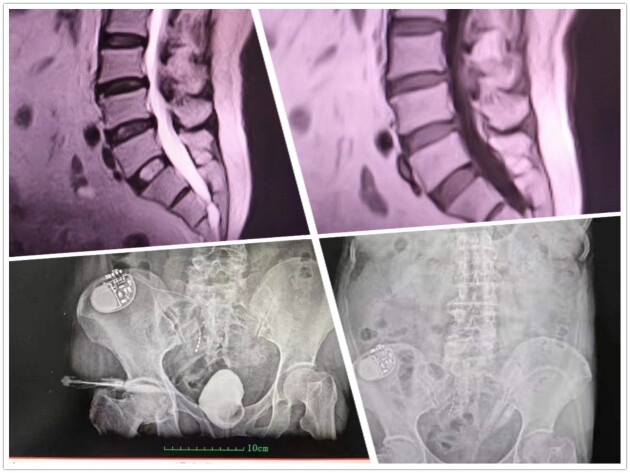

根據(jù)肖教授的經(jīng)驗(yàn),類似情況主要就是支配膀胱會(huì)陰的神經(jīng)束或神經(jīng)根受壓所致,這和坐骨神經(jīng)疼是一個(gè)道理,神經(jīng)受壓位置不同罷了。檢查結(jié)果出來后,與肖教授的分析果然相差無幾,通過脊髓核磁共振檢查,顯示患者隱性脊柱裂和骶管囊腫,異常增厚硬化的黃韌帶嚴(yán)重壓迫硬膜腔終端骶神經(jīng)束,進(jìn)而導(dǎo)致一系列病癥發(fā)生。同時(shí)經(jīng)尿動(dòng)力檢查,這位患者膀胱僅能灌入60ml,逼尿肌過度頻繁收縮,遠(yuǎn)超普通的OAB,這也是唯一有肯定療效的骶神經(jīng)刺激器置入適應(yīng)癥,患者還患有輕度的DESD(外括約肌協(xié)同失調(diào))。確認(rèn)病根病源后,肖傳國教授親自來到手術(shù)室為患者實(shí)施手術(shù)。先行骶管探查,找準(zhǔn)部位后再行囊腫切除和黃韌帶切除手術(shù)。由于這類神經(jīng)源性膀胱的骶神經(jīng)尚未完全壓榨脫失萎縮,肖教授認(rèn)為絕大部分情況并不需要實(shí)施肖氏反射弧手術(shù)。